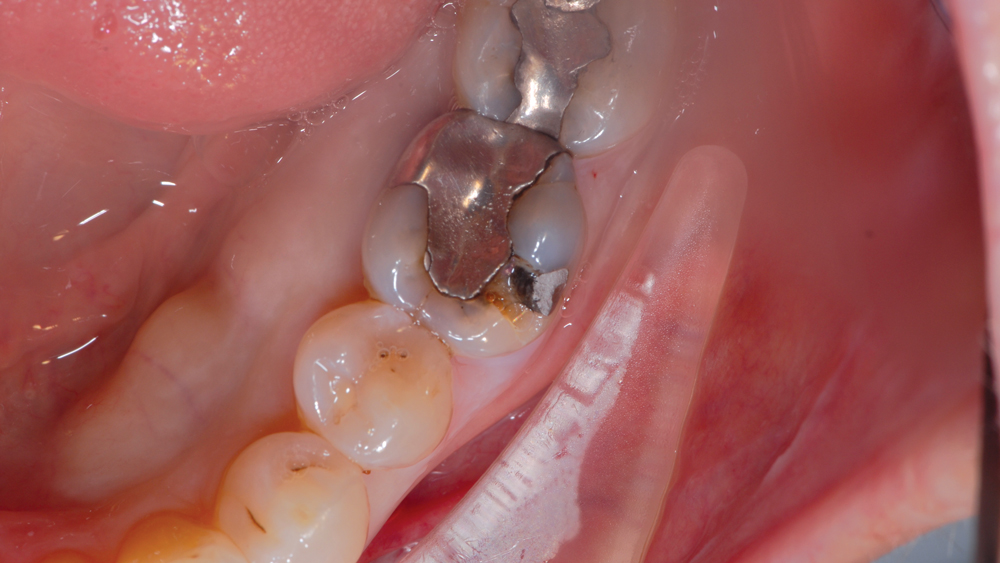

CASE REPORT

The following case highlights the efficient, user-friendly scanning capabilities of the iTero Element scanner, as well as the clinical advantages of connecting to the glidewell.io In-Office Solution for single-appointment dental restorations. The patient sought treatment for a damaged mandibular first molar with a cusp fracture. Because the case called for a single crown and high-strength zirconia, the patient was an ideal candidate for a same-visit restoration milled from a BruxZir NOW milling block. After preparing the tooth and taking an intraoral scan, the crown was fabricated within 40 minutes using the fastmill.io In-Office Unit. The final restoration fit perfectly without adjustment and exceeded the expectations of the patient, who was thrilled that she didn’t have to schedule a second appointment for the crown delivery.